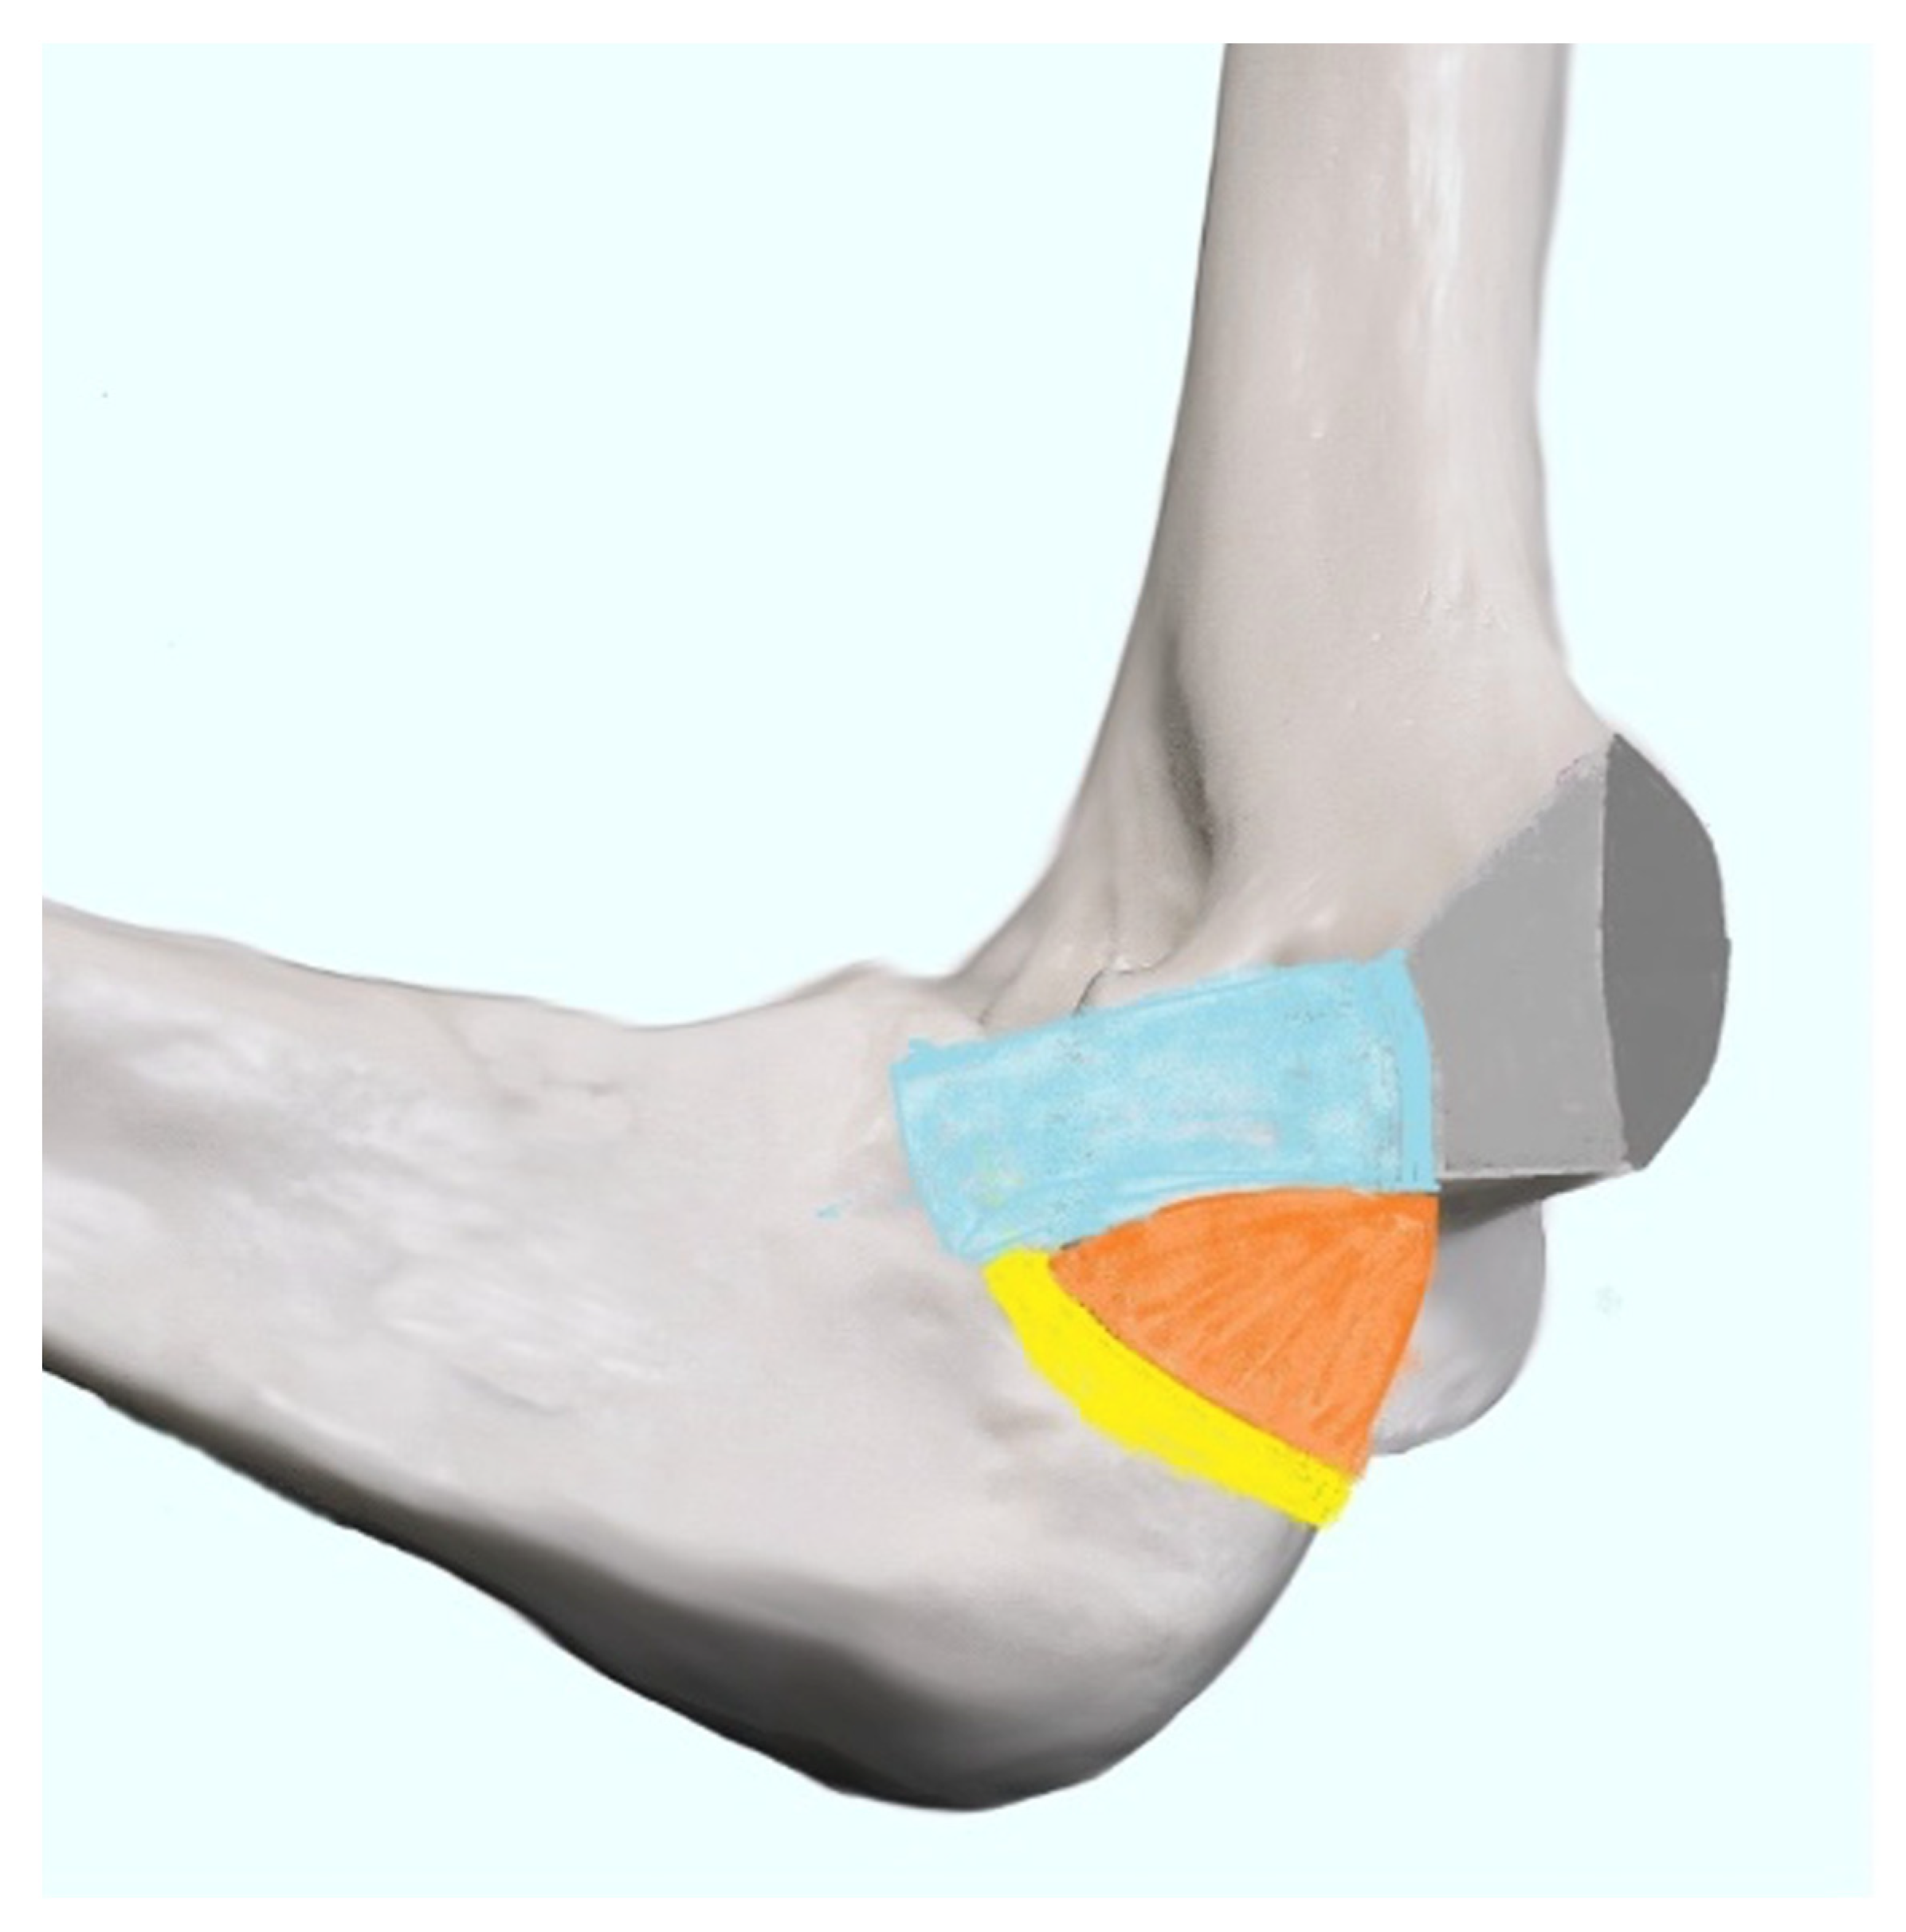

3.4.1. Normal Anatomy of the Medial Epicondyle Region

The Technique of Ultrasound Examination of the Medial Portion of the Elbow